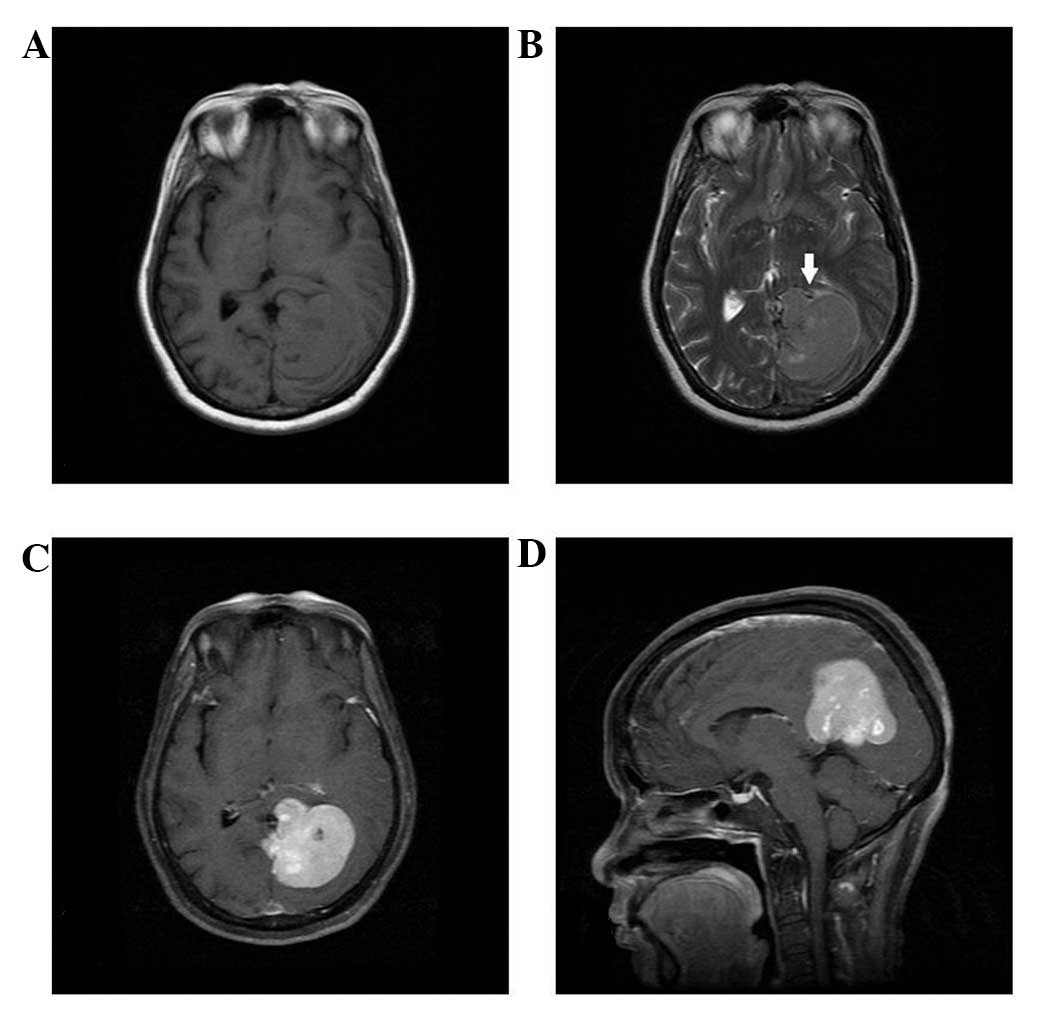

Figure 5

Patient 5. (A) Unenhanced magnetic resonance imaging scan reveals that the lesion is located in the infratentorial posterior fossa. (B) Peritumoral brain edema may be observed, and the fourth ventricle exhibits compressive change. (C) The lesion is markedly enhanced following injection of contrast agent. (D) The dural tail sign cannot be found, however, a (E) narrow-based attachment is visible and the intratumoral vessel may be detectable.

All cases were misdiagnosed as meningioma prior to surgery. MRI revealed that all five cases had a single lesion (in four cases located above the tentorium cerebelli; in one case located under the tentorium cerebelli). The lesions were lobular, measuring 3.0 to 7.5 cm with an iso-intense signal in T1WI and a slightly long signal in T2WI on the unenhanced MRI scan (Figs. 1–5). Four cases presented with a cross-midline growth pattern (Figs. 1, 3–5) and one case presented with a cross-lobe growth pattern (Fig. 2). One case exhibited dilatation of the lateral ventricle as the tumor compressed the fourth ventricle (Fig. 5). The adjacent bone was destroyed in one case (Fig. 2). Following injection of Gd-DTPA, no cases were found to exhibit the dural tail sign. Heterogeneous enhancement was observed in all cases (Figs. 1–5). Cystic degeneration, necrosis as well as flow void were observed in all cases (Figs. 1–5). The detailed MRI findings are listed in Table II.